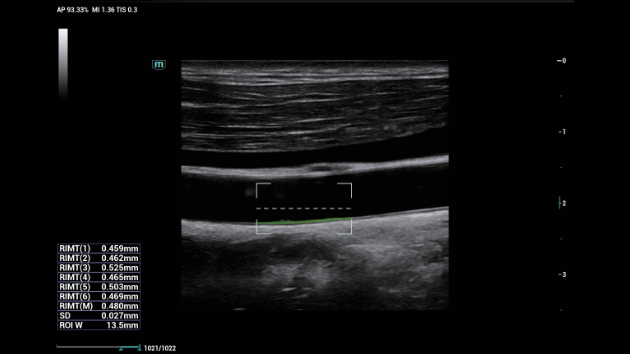

Soluzioni di diagnostica per immagini complete con tecnologia ZST+

La piattaforma ZST+ è un'innovazione straordinaria, che rappresenta un'evoluzione nel campo dell'ecografia. Grazie alla trasformazione delle metriche a ultrasuoni dal beamforming convenzionale all'elaborazione basata sui dati di canale, supera la tradizionale limitazione del trade-off tra risoluzione spaziale, risoluzione temporale e uniformità dei tessuti, offrendo una qualità d'immagine eccezionale per infinite soluzioni di imaging con miglioramenti continui.